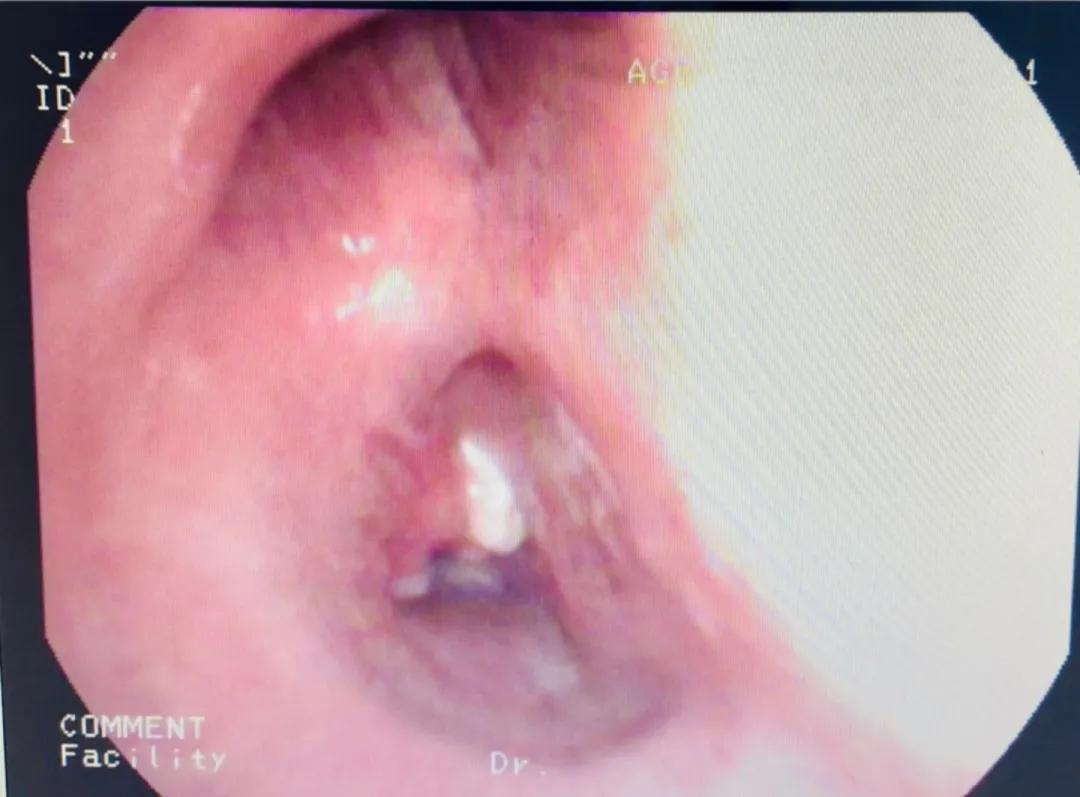

在专家的现场指导下,吴西雅顺利地将硬镜插入右肺中叶。接下来的操作因为有了硬镜鞘管的气道保护和操作孔道,软镜和冷热消融操作较稳妥。1小时后,李先生右肺下叶支气管顺利打通。术毕患者约50分钟后清醒,气促情况明显缓解,状态良好,未感特殊不适。

操作前(左)后(右)照片对比